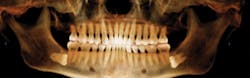

This is an example of what a typical panoramic image created using a CBCT scan looks like.

Showing parents that their child has impacted canines on a 2-D panoramic image isn’t always clear and obvious. However, a 3-D image can be spun around from front to back and left to right to clearly show patients and their parents the impacted canine. The software even enables us to peel back layers that may be obstructing the view, which allows for the most accurate diagnosis. When parents are able to see and understand these factors, they usually can’t wait to schedule their child’s orthodontic treatment.